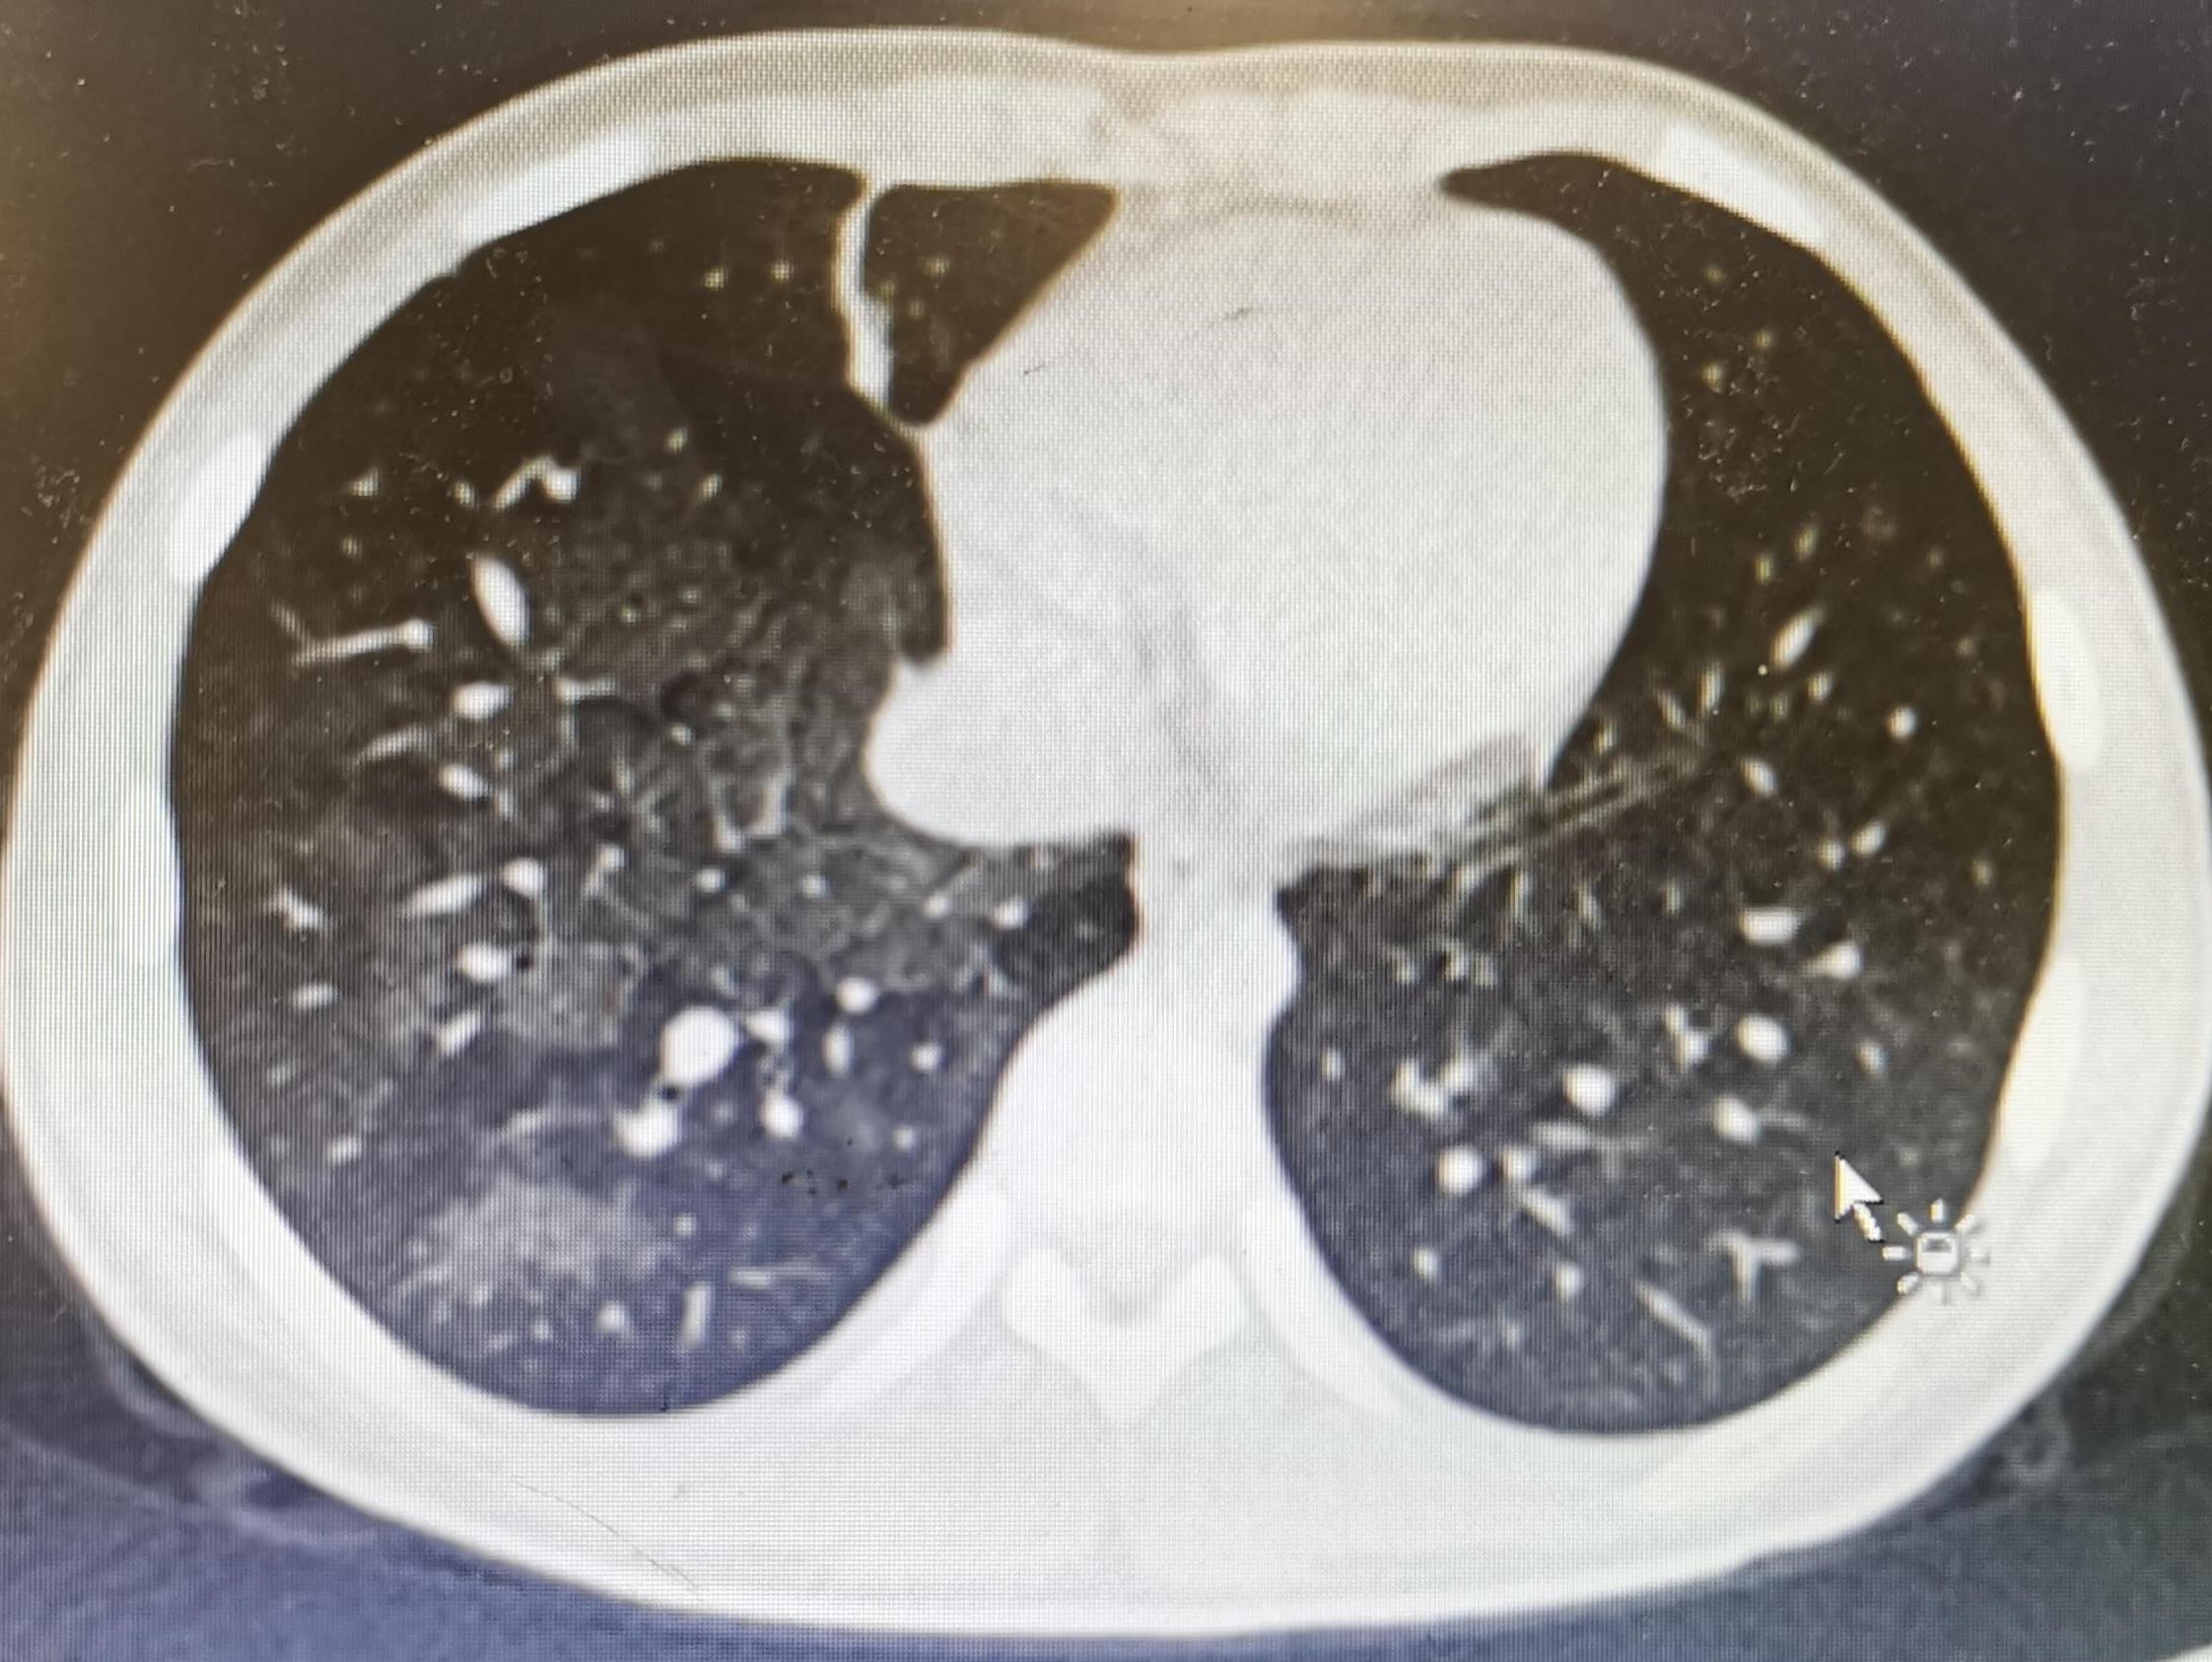

患儿女,因“咳嗽伴咯血”入院。入院2天前出现阵发性咳嗽,咯血,鲜红色血液、量多,无鼻衄,无发热,无呕血,胸部CT示双肺磨玻璃样改变。因考虑吸入性肺炎,当地给予“罗氏芬、甲强龙”治疗,但治疗效果较差。就诊我院儿科门诊,以“重症肺炎,支气管异物”于3月17日收入院。

入院后经科室讨论,患儿急性疾病,无发热,炎症指标无明显异常,咯血鲜红色,无鼻衄及呕血,呼吸道出血可能性大,为明确诊断,于3月18日行支气管镜检查,镜下气管管腔可见血性物质,右肺中叶内侧段开口处可见鲜红色流出,余亚段未见血性物质,出血部位为右肺中叶内侧段,考虑肺血管畸形所致可能性大。为明确诊断和下一步介入治疗提供依据,3月19日行肺动脉CTA,示肺动脉CTA未见异常,双肺磨玻璃密度改变。